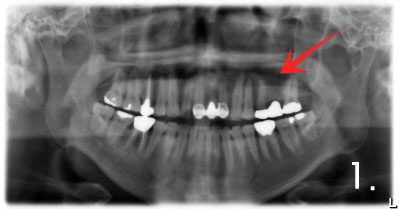

Before the surgery. There is not enough bone at back site to place implants

Implant placement and sinus bone graft were performed simultaneously on right side. Only sinus bone graft was performed on left side due to the lack of the residual bone to place implant simultaneously

Implant placement was performed a few months after sinus bone graft